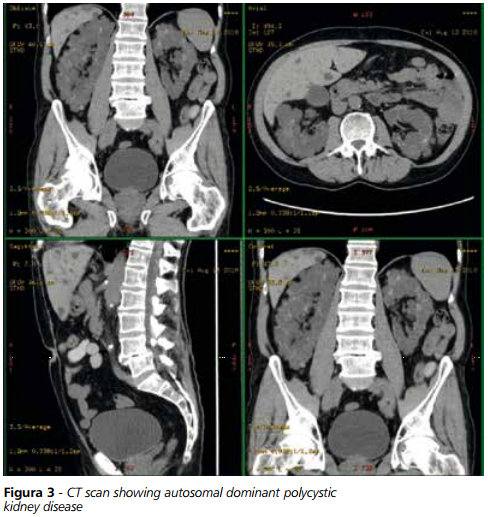

MINETTI – Il rene policistico autosomico dominante (ADPKD) per i nefrologi rappresenta una patologia di grande interesse, essendo la più frequente condizione ereditaria che interessa il rene, caratterizzata da una evoluzione progressiva verso l’insufficienza terminale di organo. Colpisce circa 4 persone ogni 10.000 ed in questo senso può essere considerata una malattia “rara”, anche se i riscontri autoptici parlano di cifre molto più alte a causa del grande numero di casi che rimangono asintomatici in relazione alla penetranza della malattia. La forma più frequente, riscontrata in circa l’85% dei pazienti, è quella autosomica dominante in cui si ha una mutazione che interessa il gene posto sul cromosoma 16 che codifica per una proteina chiamata appunto policistina. Il restante 15% dei casi si riferisce ad una alterazione di un gene posto sul cromosoma 4 che codifica per un’altra proteina definita policistina 2. A questi due quadri di alterazione genetica si legano i differenti comportamenti nell’andamento clinico della malattia.

MINETTI – Un aspetto importante da valutare quando si esaminano le potenzialità di una nuova molecola è certamente rappresentato dalla selezione dei pazienti nei quali impiegarlo. Come già detto un criterio di valutazione importante nella stadiazione della malattia policistica renale è la misurazione del volume del rene o dei reni interessati. Oltre alle normali metodiche radiologiche che ne misurano i diametri antero-posteriore, longitudinale o trasverso, disponiamo oggi di metodiche TAC che, basate sull’impiego di appositi software, riescono a misurare con grande esattezza il reale volume dell’organo malato. Si tratta di tecniche ancora non del tutto entrate nella comune pratica clinica, che comunque necessitano della collaborazione partecipata di radiologi specificamente a conoscenza dei diversi aspetti della malattia.